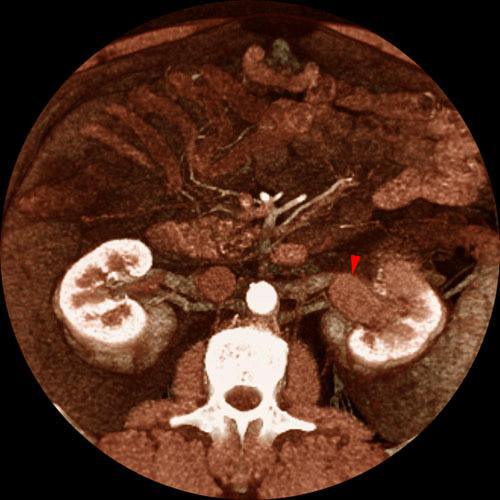

Tumor renal. Invasión de vía urinaria

VR seccional. Visión axial caudal. Infiltracion de pelvis renal izquierda (punta de flecha), secundaria a la invasión por contiguidad de un hipernefroma